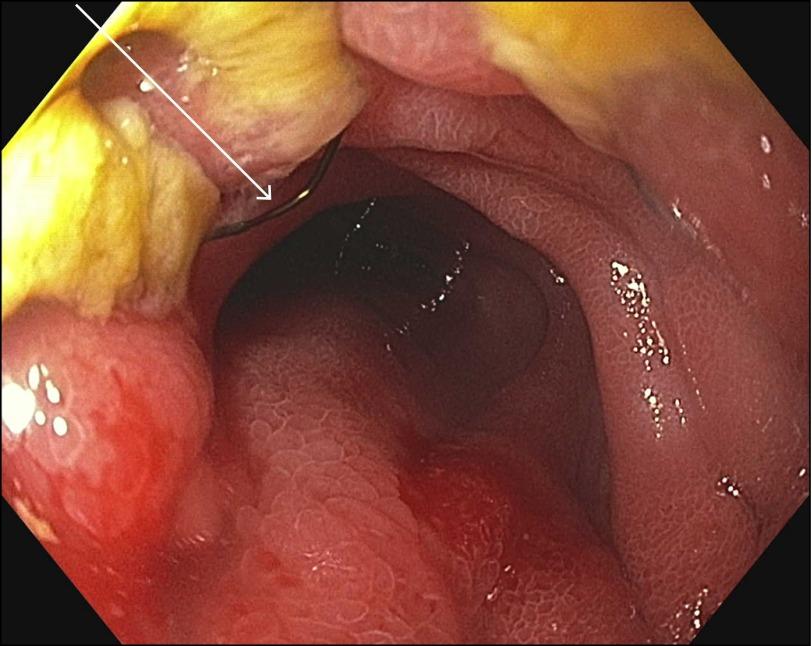

Novel Treatment of Malignant Gastric Outlet Obstruction With a Stent-Within-Stent Approach Secured With Apollo OverStitch™.

https://cdn.ncbi.nlm.nih.gov/pmc/blobs/5245/5062678/3cdeb58c4106/CG-CGCR160055F001.jpg